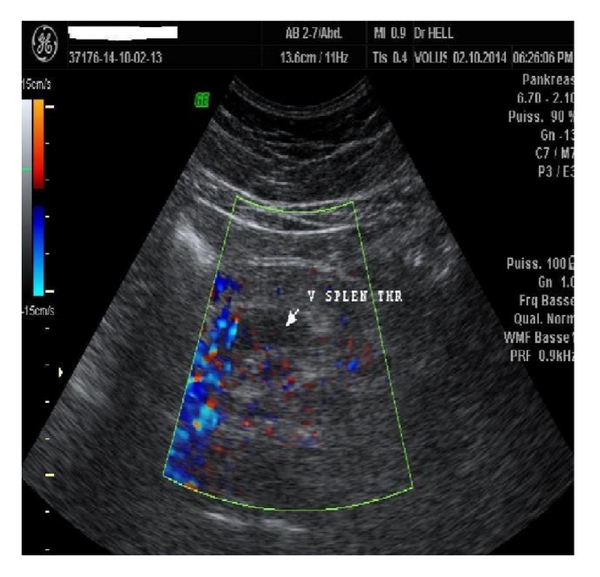

A 46-year-old Cameroonian man, living in North Cameroon, was admitted to the Yaoundé University Teaching Hospital for diffuse abdominal pain accompanied by abdominal distension and vomiting for three-week duration. This was treated as a gastroduodenal ulcer without accurate diagnosis on endoscopy. His past medical history was unremarkable. The physical exam revealed a distended and tympanic abdomen, diffusely tender with no guarding. There was no palpable mass and bowel sounds were present. The digital rectal exam elicited pains on both sides. On admission, he has a low grade fever with a temperature of 38.2°C; the blood pressure was 113/82 mm Hg, and the heart rate 102 beats/minute. The laboratory tests (hemogram and biochemistry) were normal except for a C-reactive protein of 160 mg/L (standards: less than 6 mg/L), the lipase of 6xULN (upper limit of normal), and mild hepatic cytolysis (ALT greater than 3xULN). The tests of the hepatitis B surface antigen, the anti-hepatitis C virus antibodies, and the human immunodeficiency virus (HIV) were negative. Abdominal Doppler ultrasonography revealed an extensive venous thrombosis of the portal, splenic, and mesenteric veins (Figure 1). The abdominal contrast-enhanced CT scanner confirmed the extended thrombosis and highlighted an infiltration of the proximal pancreas associated with inflammatory flows in the peritoneum (Figure 2).

The combination of Doppler ultrasonography and CT scanner increases the diagnostic sensitivity. Doppler ultrasonography and CT scanner have a negative predictive value of 98% and 100%, respectively. Both tests enable showing pseudoaneurysm, intrapseudocystic bleeding, intra-abdominal collections, venous thrombosis, and varices [11, 12]. We performed both exams for diagnosis in this case.